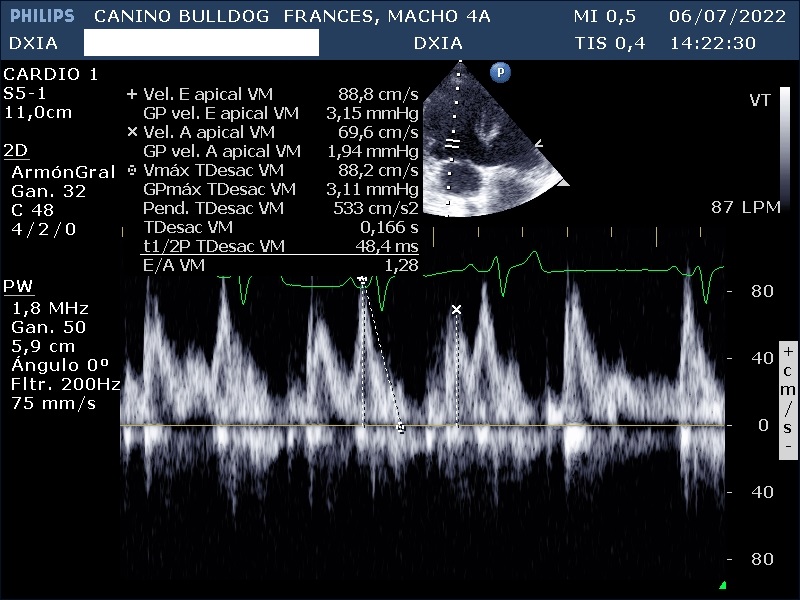

- Válvula mitral: Normoimplantada. No se detectan engrosamientos valvulares, pero las valvas no coaptan correctamente. Estudio Doppler con flujo de regurgitación moderado-severo de Vmáx RM: 504 cm/s y GPmáx RM: 102 mmHg.

Dilatación marcada de cámaras derechas e izquierdas. SSPE VM: 0,952 cm